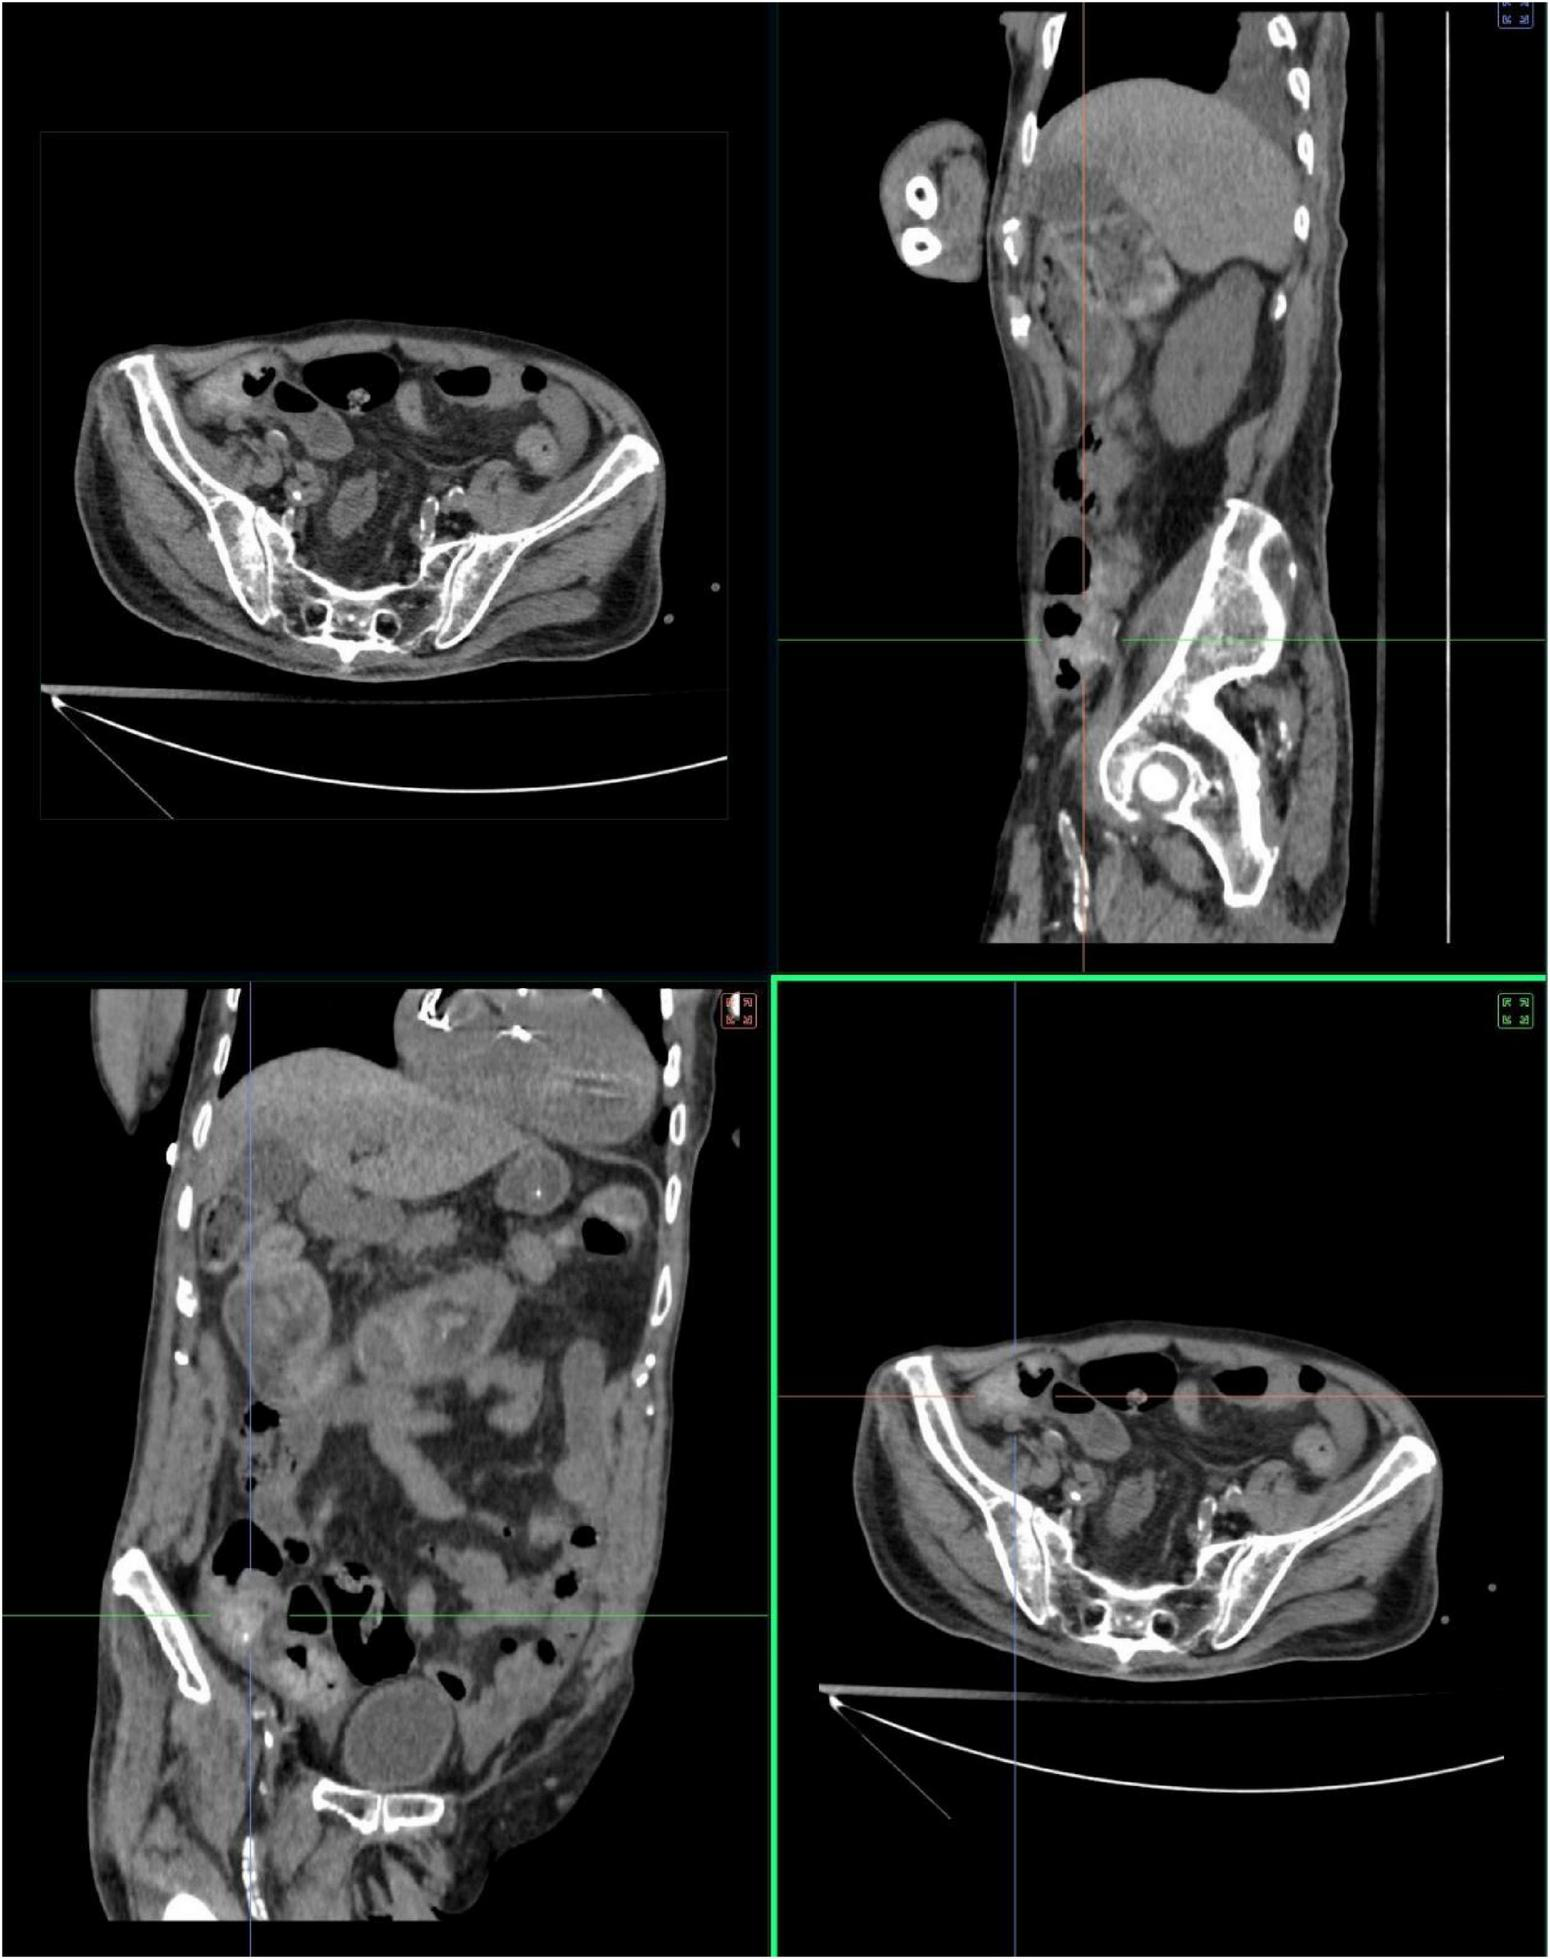

2 Patient information and conventionl management

A 90-years-old male COVID-19 patient was admitted to the hospital on December 29, 2022. In addition to fever and respiratory symptoms, he presented with abdominal distension, failure to pass flatus or stool for 48 h, and reduced food intake, accompanied by a desire to vomit. The circumference of his abdomen was measured at 90 cm. An initial abdominal scan revealed evidence of low intestinal obstruction that colon and small intestine show marked dilation with fluid accumulation; no definite mass lesion is identified. The widest portion of the colon at the horizontal level measures 90.71 mm × 110.78 mm (Figure 2). Blood pressure upon admission was 90/58 mmHg, Hemoglobin: 87 g/L, Platelets: 92/L, Sodium: 135 mmol/L, C-reactive protein (hs-CRP): 47.32 mg/L, Serum creatinine was 190 umol/l, and the glomerular filtration rate was 27.69 mL/min calculated according to the MDRD formula. Quantitative determination of B-type natriuretic peptide (BNP): 505 pg/ml. His medical history included 20 years of type 2 diabetes (managed with insulin), 2 years of chronic heart failure (treated with sacubitril/valsartan, furosemide, spironolactone), 2 years of benign prostatic hyperplasia (treated with finasteride, doxazosin), and gastrointestinal ulcers (treated with rabeprazole). He had a pacemaker implanted 11 years ago and had a documented penicillin allergy. Significantly, the patient had a 5-years history of chronic constipation.

FIGURE 2

The CT thin-layer scan images were reconstructed using multiplanar reconstruction. From multiple angles such as the transverse section, sagittal section, and coronal section, the degree of intestinal dilation, the distribution of the air-fluid level, and the measurement value of the maximum dilated intestinal segment (110.78mm * 90.71mm) were observed.

Figure 2. Admission sagittal CT of the abdomen demonstrating intestinal obstruction, characterized by multiple air-fluid levels within dilated bowel loops and marked abdominal distension. The widest part of the horizontal plane was 90.71 mm × 110.78 mm.